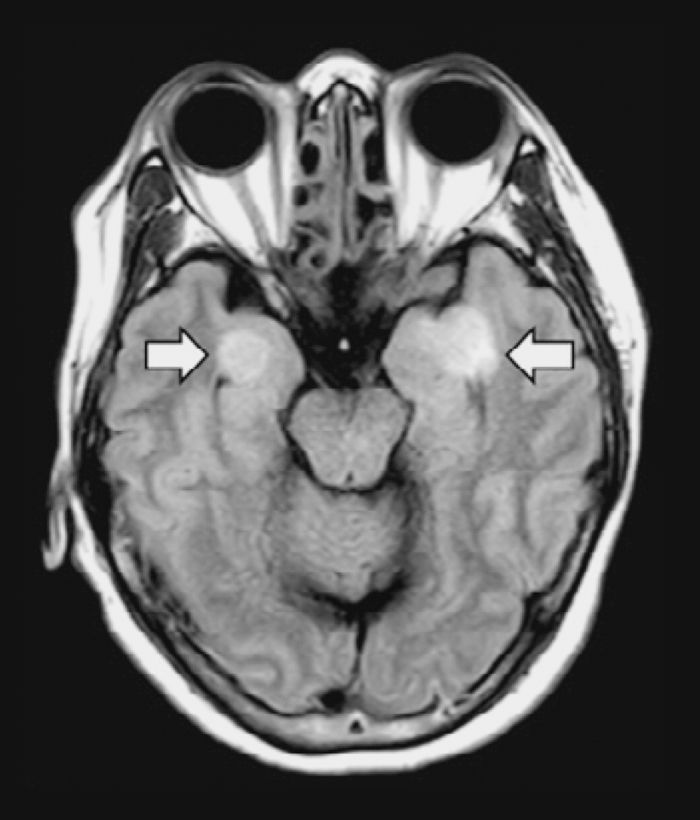

此外,新冠病毒如何影响大脑,是医护人员正在努力解决的另一个主要问题。相当一部分患者出现癫痫发作和脑部肿胀,但目前还不清楚病毒是如何攻击脑干或神经皮层的,而这两个部位都有ACE2受体,病毒可能会附着在这两个部位,也不清楚病毒是否会扩散到保护中枢神经系统许多重要部位的脑脊液。有可能是病毒对血液的影响最终导致了大脑中的反应,因为血块可能会引起肿胀,并引发任何一系列严重的神经系统症状。